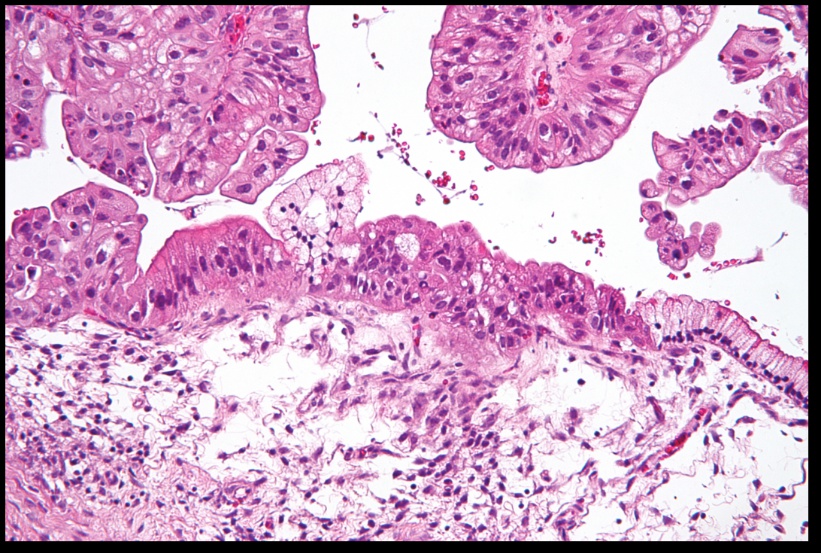

Serous cystadenoma of the ovary. On microscopic examination, the cyst is lined by a single layer of ciliated tubal-type epithelium.

Serous cystadenocarcinoma. A higher-power view shows the laminated structure of a psammoma body.